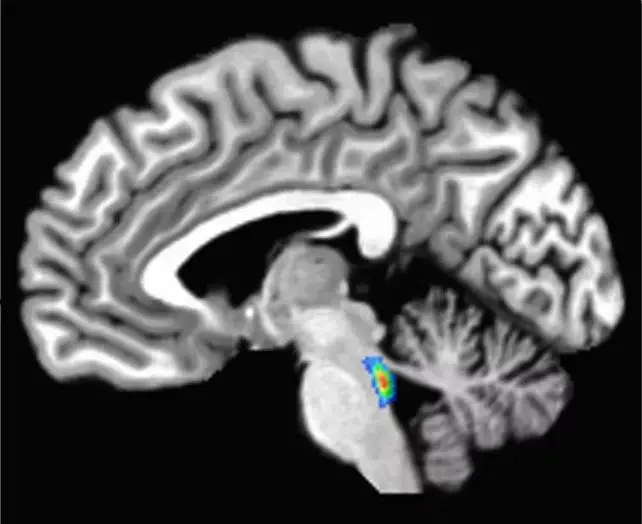

В центре внимания исследователей находится небольшая структура мозга под названием locus coeruleus, расположенная в стволе мозга. Эта область продуцирует норадреналин — химическое вещество, необходимое для функционирования процессов сна, бодрствования, внимания и иммунной защиты. Именно в locus coeruleus начинается накопление белка тау примерно в возрасте 30 лет, что предшествует развитию болезни Альцгеймера на десятилетия.

Блуждающий нерв напрямую связан с locus coeruleus, передавая сигналы между мозгом и органами грудной полости, включая сердце и лёгкие. Стимуляция этого нерва оказывает регулирующее воздействие на активность нейронов в указанной области мозга, позволяя им функционировать оптимально.